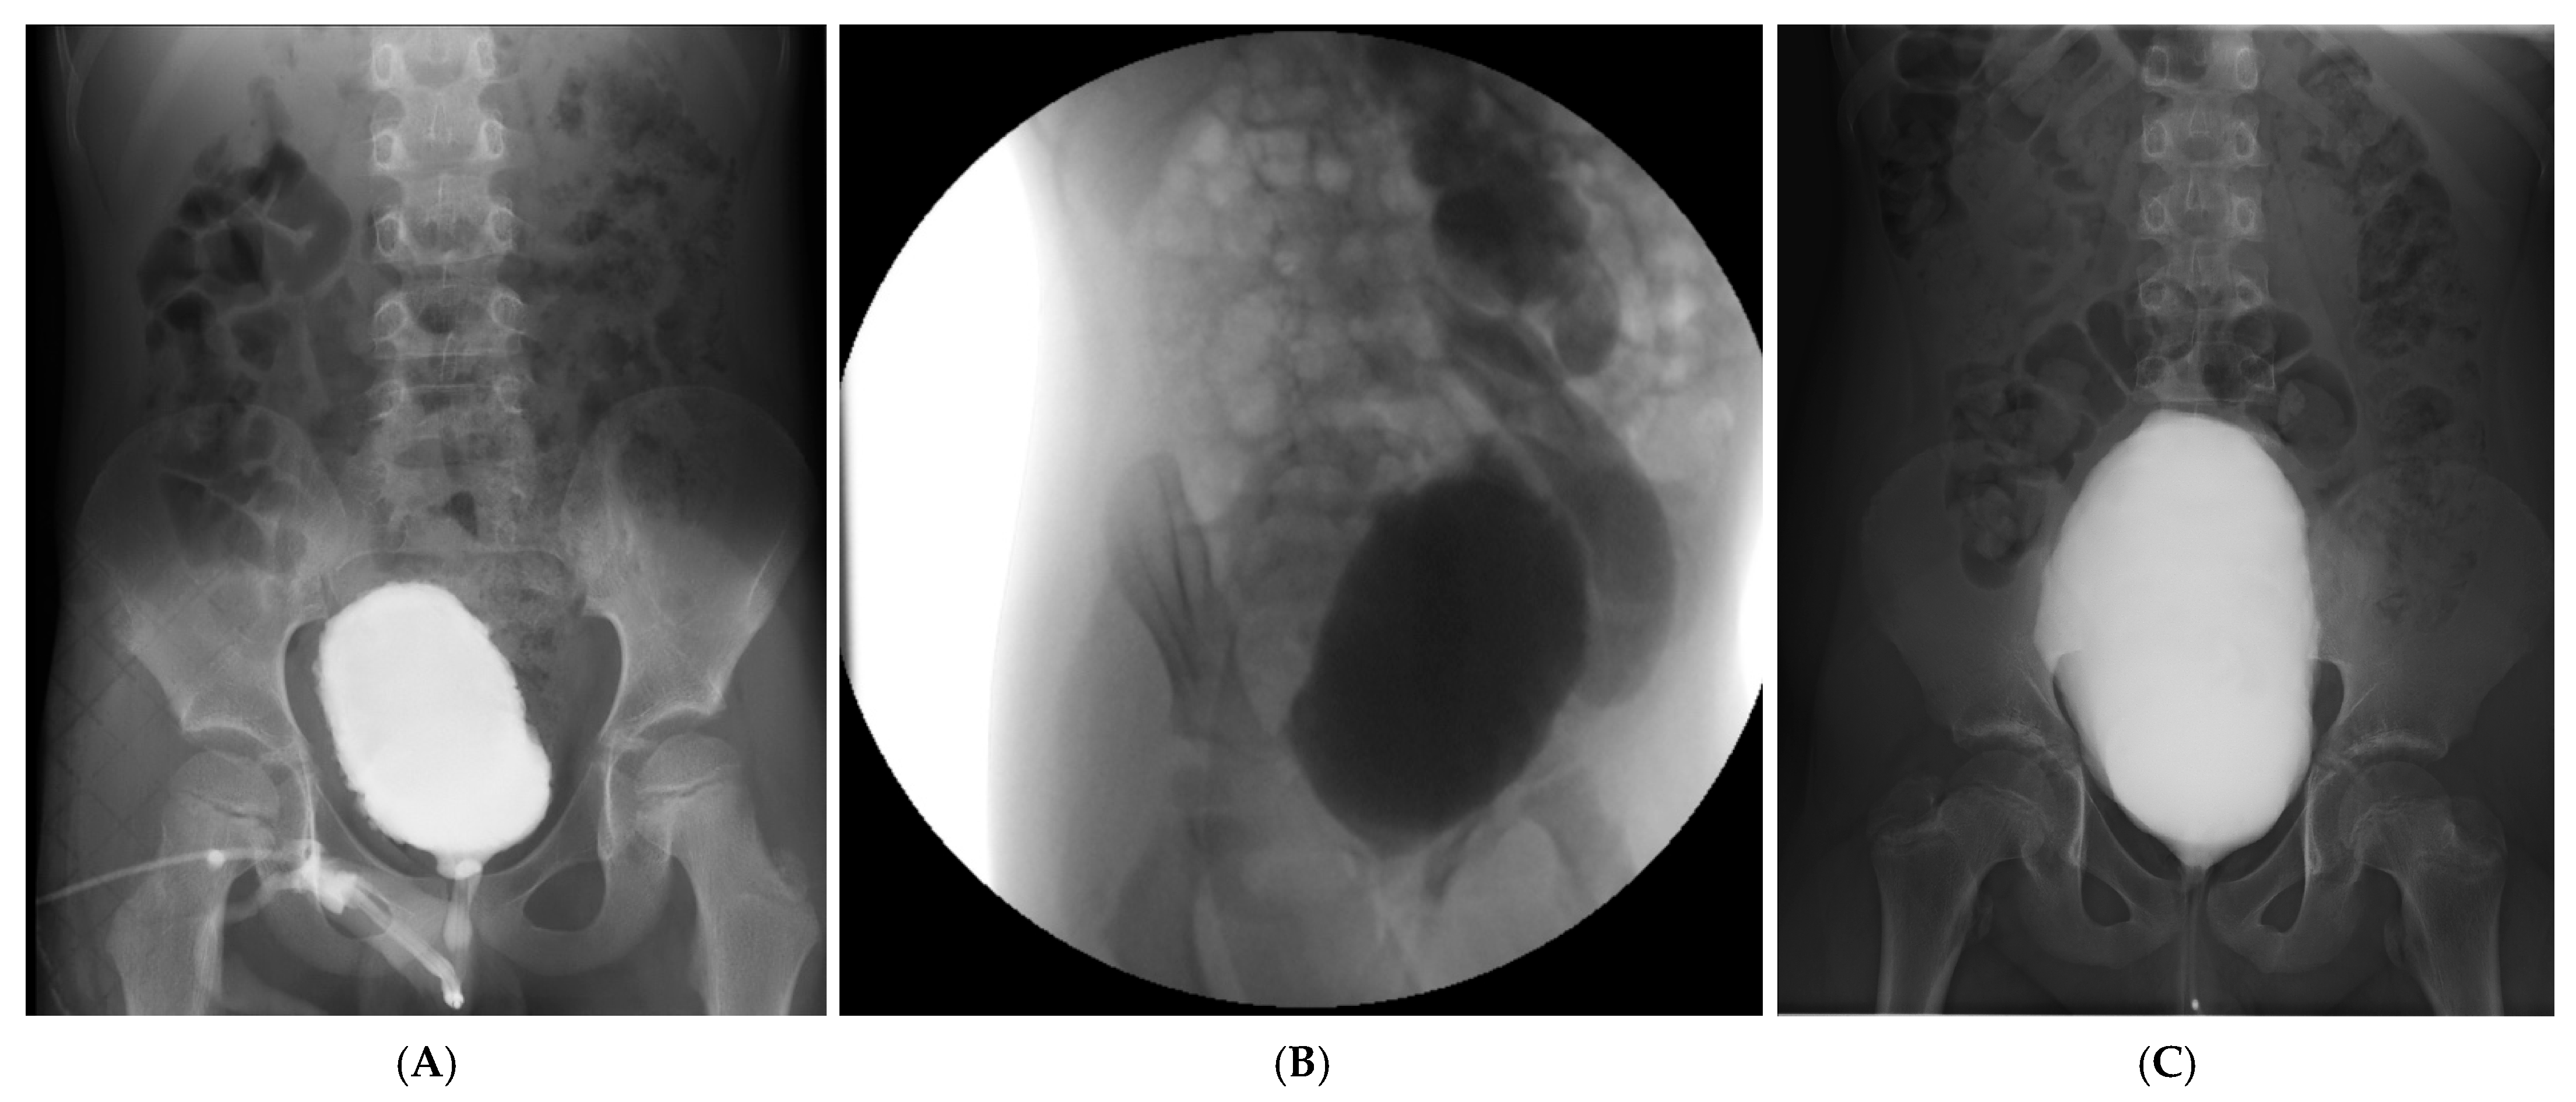

| VCUG Findings | Crenulated bladder, no reflux, normal emptying | Grade V left VUR, dilated tortuous ureter, no voiding achieved | Large-capacity bladder, mild crenulation, grade I VUR, incomplete emptying |